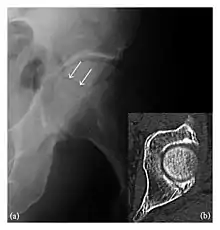

Occult osseous injuries may result from a direct blow to the bone by compressive forces of adjacent bones against one another or by traction forces during an avulsion injury. Lesions in the tibial plateau, hip, ankle, and wrist are often missed. In a tibial plateau fracture, any disruption of the posterior and anterior cortical rims of the plateau should be sought. Impaction of subchondral bone will appear as an increased sclerosis of the subchondral bone (Figure 1). In the hip, posterior acetabular fractures also present subtle radiographic findings. The acetabular lines should then be carefully examined keeping in mind that the posterior rim, which is harder to see on X-rays, is more frequently fractured than the anterior rim (Figure 2). In the wrist, detection of carpal bone fractures is often challenging, with up to 18% of scaphoid fractures radiographically occult. Carpal fractures, especially the scaphoid, are associated with the risk of avascular necrosis. In apparently normal wrist radiographs from symptomatic patients, if there is history of a fall on an outstretched hand with pain in the anatomic snuffbox, suggesting scaphoid injury, the initial examination with posteroanterior, lateral, and pronation oblique views must be complemented by other specific views such as supination oblique and the "scaphoid" view A careful examination of cortices for evidence of discontinuity or offset and cancellous bone for lucency is necessary (Figure 3).[1]

The greater tuberosity of the humerus is also an illustrative location of occult fractures. The osseous injury may follow seizures, glenohumeral dislocation, forced abduction, or direct impaction. They are commonly discovered on MRI in symptomatic patients with suspicion of rotator cuff tear. Coronal images are best suited for detection. They appear as crescentic oblique lines surrounded by a bone marrow edema pattern (Figure 5). The rotator cuff must be inspected since associated ligamentous lesions are common. In the ankle, malleoli and tarsal bones should be checked carefully for any cortical disruptions and radiolucent lines that may reveal a fracture. Awareness of the exact location of the pain will help direct the attention of the interpreter when searching for very subtle signs of fracture (Figure 6).[1]

a

b

Figure 6: Subtle anterior talar fracture in a 39-year-old man presenting with ankle pain after a fall. (a) Anteroposterior radiograph shows a subtle oblique radiolucent line through the talus (white arrows). (b) Sagittal CT reformation confirms the presence of an anterior talar fracture with cortical offset (black arrow). Avulsion fractures, which consist of a detached bone fragment resulting from a ligament or tendon pulling away from the bone, may also present with subtle radiographic signs. Tiny osseous fragments near the presumed attachment site of a ligament suggest this diagnosis. Common sites are the lateral tibial plateau (the Segond fracture), the spinal tuberosity of the tibia resulting from anterior cruciate ligament avulsion, and the ischial tuberosity.[1]